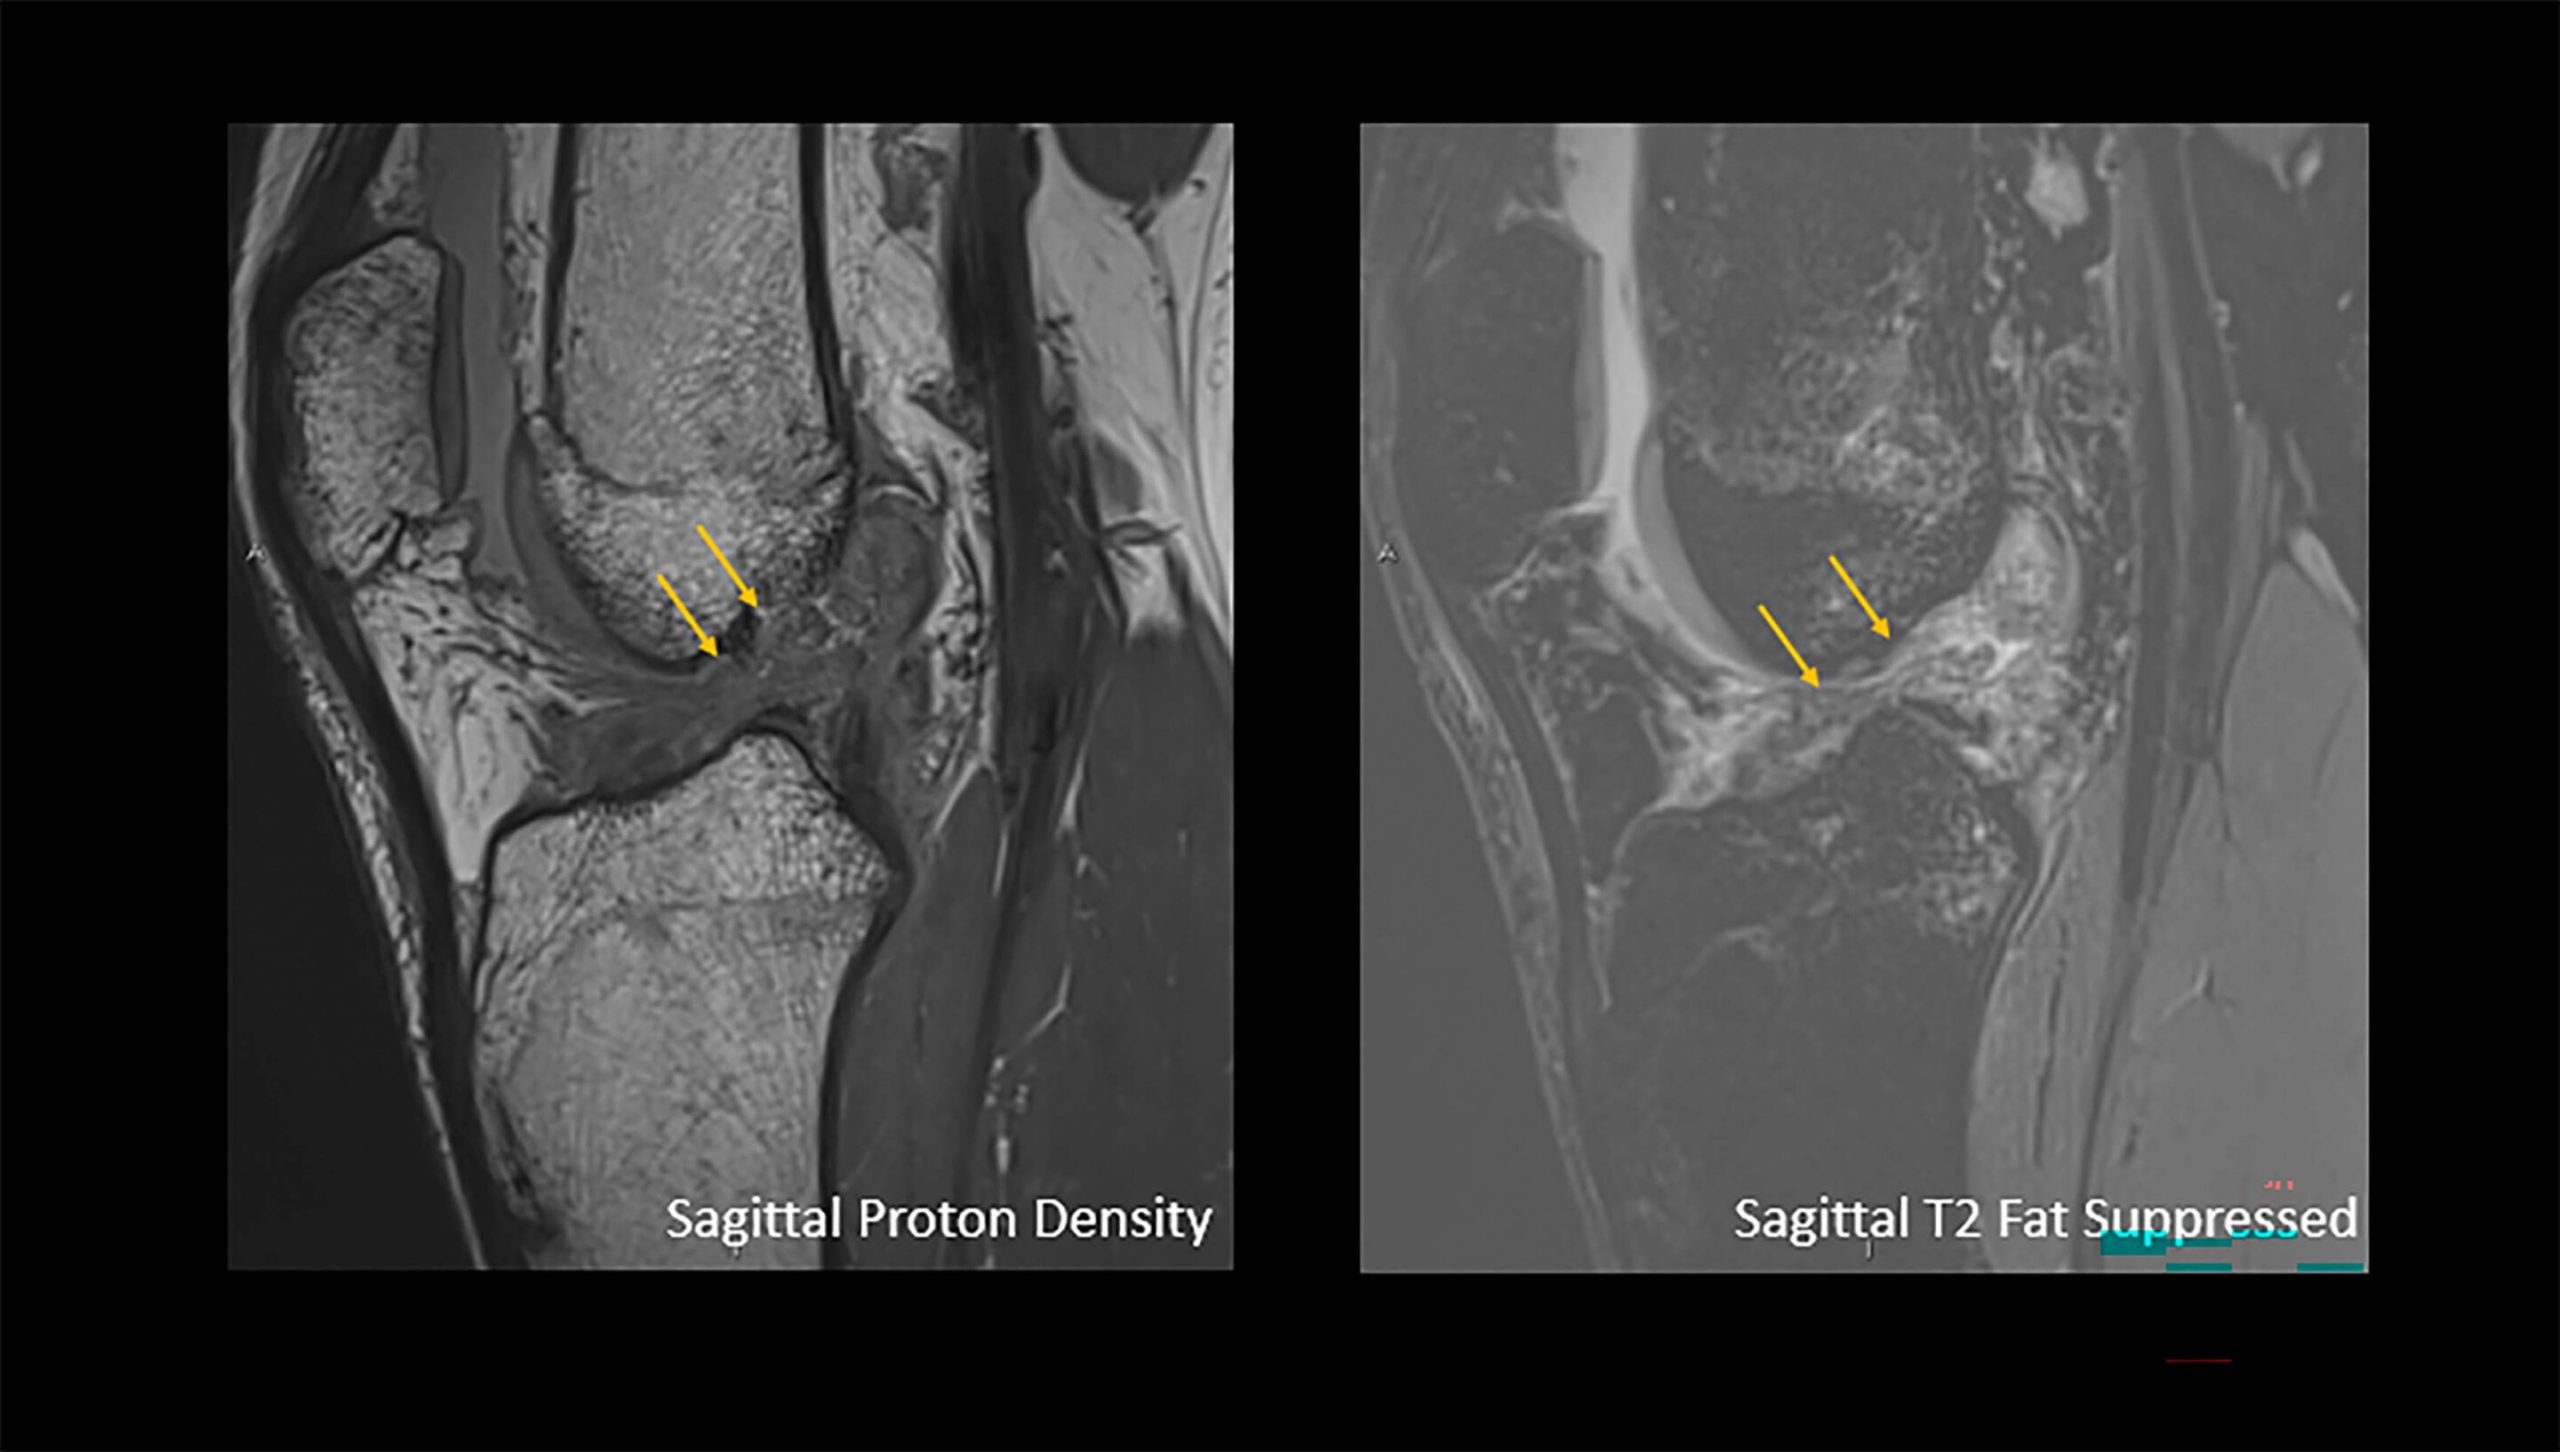

Исследование включало 13 549 последовательных плановых МРТ-исследований коленного сустава, проведенных в период с 2019 по 2024 год в четырех амбулаторных радиологических отделениях больницы Джонса Хопкинса. Пациенты отмечали боль в колене как основную жалобу.

Исследователи извлекли следующие признаки из отчетов рентгенологических исследований: разрывы или травмы медиального и латерального менисков, передней крестообразной связки (ПКС), задней крестообразной связки, медиальной коллатеральной связки (МКС), комплекса латеральной коллатеральной связки, а также разгибательного механизма или вывиха надколенника и бедренной кости.

Мениски — это С-образные хрящевые прослойки на внутренней (медиальной) и наружной (латеральной) сторонах колена, которые действуют как амортизаторы, смягчая удары и обеспечивая стабильность сустава. Разрывы менисков могут возникать при подворачивании или в результате постепенного износа с течением времени.

Анализ отчетов МРТ показал, что определенные травмы чаще наблюдались у мужчин по сравнению с женщинами, включая разрывы только передней крестообразной связки, разрыв передней крестообразной связки с разрывом медиального мениска или разрыв передней крестообразной связки с разрывом латерального мениска.